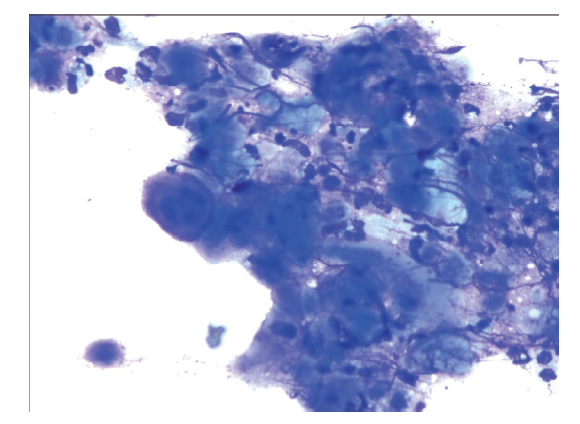

白细胞9.72×109 /L,CRP 144 mg/L,血清淀粉样蛋白> 200 mg/L,降钙素原0.391 ng/ml,细胞免疫 CD3计数、CD4计数、CD8计数均降低(CD3计数 326/μL、CD4计数 165/μL、CD8计数161/μL)。肝肾功能、电解质、尿常规、大便常规未见明显异常。HIV抗体阴性。泌尿系统彩色多普勒超声(彩超)、肝胆脾胰彩超、双下肢动静脉彩超正常。胸部CT示双侧腋窝多发淋巴结肿大,盆腔CT示双侧髂血管区、腹股沟多发淋巴结肿大。皮损病理活组织检查示表皮内水疱形成,个别疱核见核内包涵体,真皮未见明显炎症反应(图2A、B)。皮损疱底刮取物细胞学涂片检查示较多中性粒细胞、淋巴细胞,可见多核巨细胞及核内包涵体(图3)。

图3 一例播散性带状疱疹患者皮损疱底刮取物细胞学涂片

本例患者既往有类风湿关节炎病史数10年,一直规律口服甲氨蝶呤5 mg/次,2次/周,入院后实验室检查提示细胞免疫功能明显受抑制。该患者初始皮损发生于左大腿,伴针刺样疼痛,后皮损逐渐播散到其他部位,仔细观察皮损初起为丘疹、丘疱疹,但皮损很快出现破溃、结痂,局部还有淤点、淤斑等出血性损害。皮损病理活组织及疱底刮取物细胞学涂片检查均提示疱疹病毒感染。结合病史、皮损特征符合播散性带状疱疹诊断。因本例患者免疫功能明显受限,故该患者病程明显延长、皮损广泛,关键是初发皮损很快演变为溃疡、结痂,而且局部有淤点、淤斑等出血性损害,同时还伴有疼痛,故初诊时误诊为血管炎。皮肤血管炎是一大类皮肤病,皮损表现与受累血管大小、范围及炎症程度相关,也可表现为紫癜、丘疹、红斑、结节、溃疡、坏死等,常见的主观症状为疼痛[5]。但组织病理学主要表现为血管壁及血管周围炎性细胞浸润,并伴有血管损伤,包括纤维素沉积、胶原纤维变性或坏死、内皮细胞肿胀等[6]